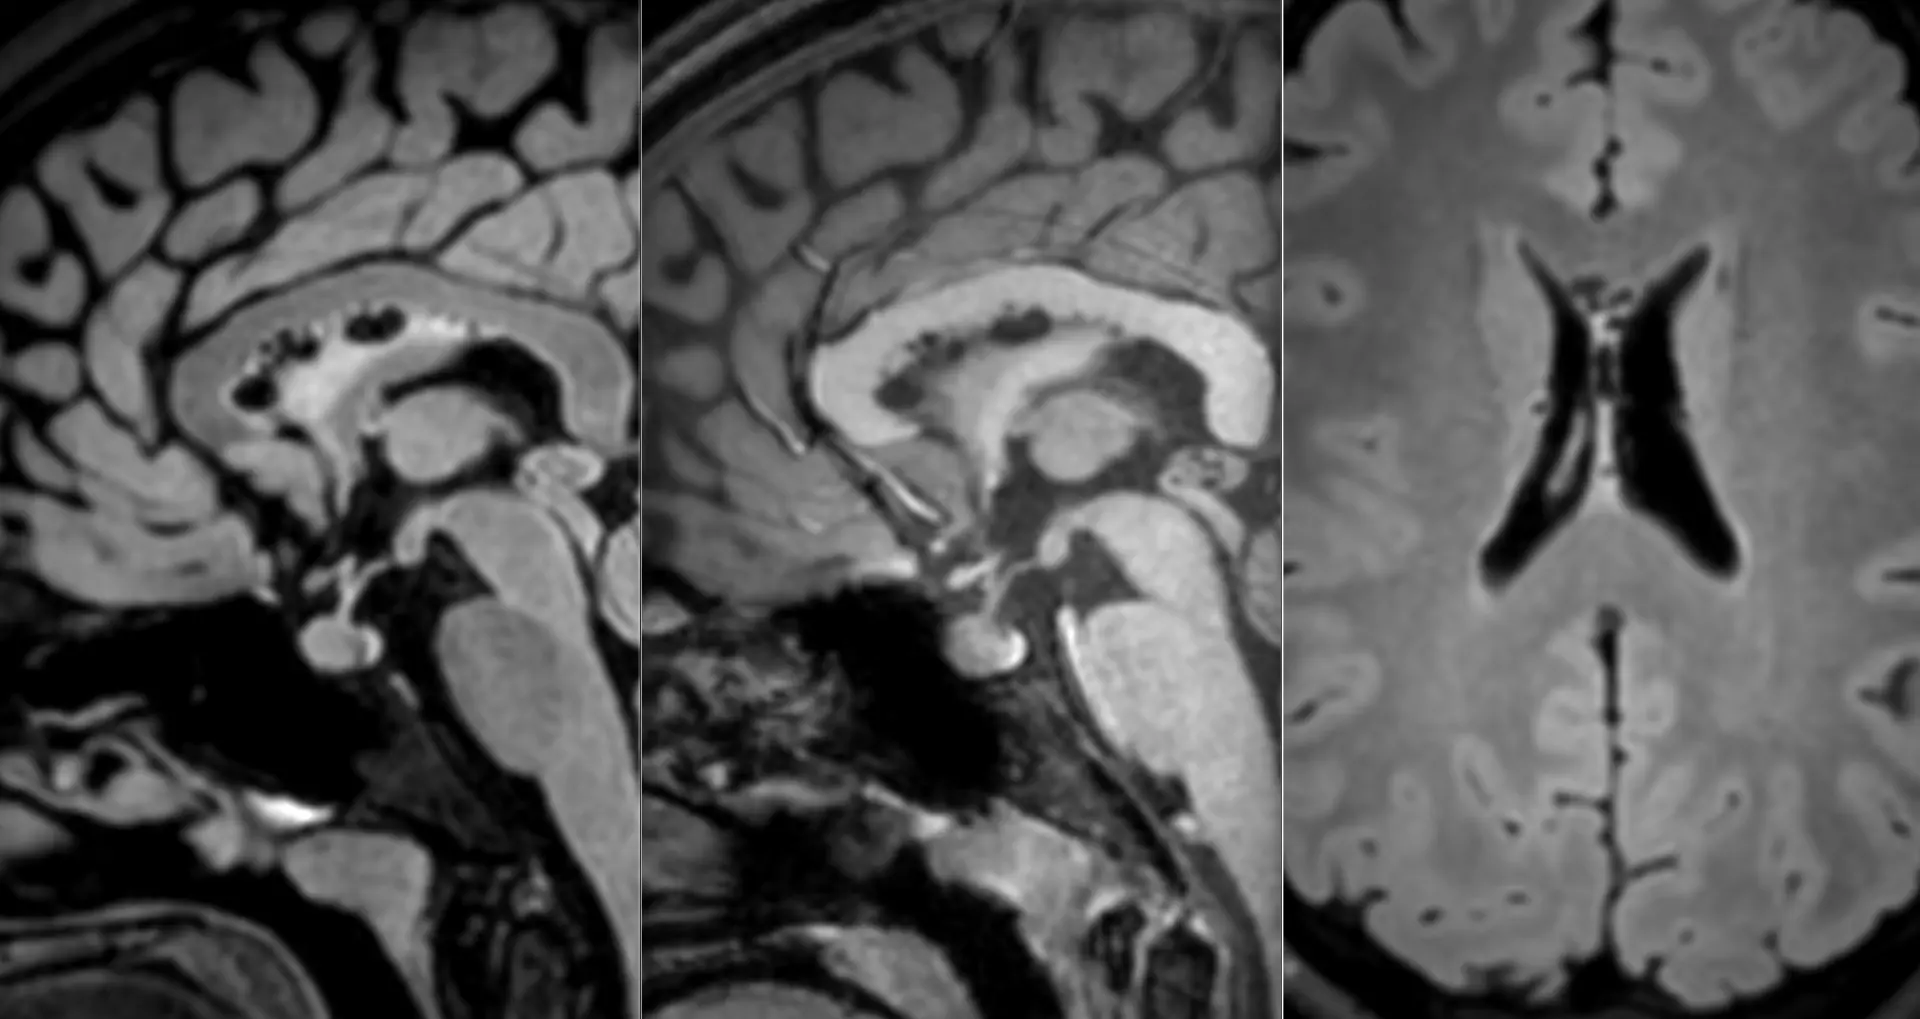

Наконец-то я увидел это воочию! Киста полости Верги, промежуточного паруса, осложнённая гидроцефалией. Из анамнеза: Низкое артериальнео давление, нарушение речи, затуманенное сознание, головная боль, головокружение, в 1989 году перенёс менингит.

А Вы видали такое? Я впервые вижу, раньше только читал в литературе.